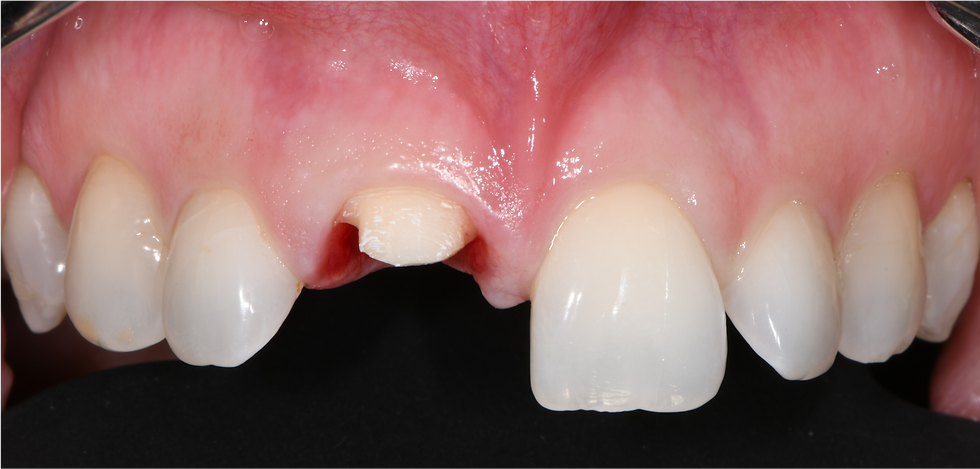

Pre-op clinical image

Detail of pre-op clinical image

Traumatic fracture of element 1.1